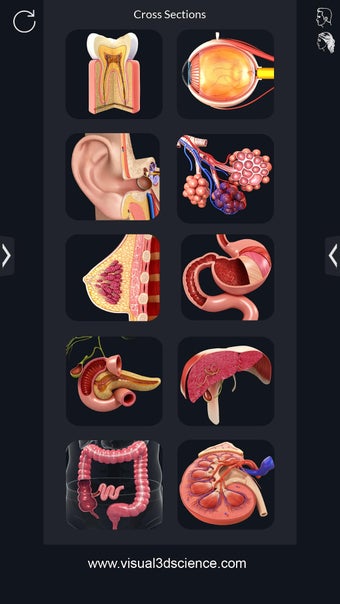

My Organs Anatomy es una aplicación de anatomía 3D gratuita desarrollada por Visual 3D Science para usuarios de Android. Esta aplicación proporciona un modelo 3D altamente realista de los órganos humanos que se puede girar 360°, acercar y alejar, y ver desde cualquier ángulo. La aplicación está diseñada para proporcionar una mirada detallada a la anatomía de los órganos humanos y ofrece varias características para ayudar a los usuarios a explorar y aprender.

La interfaz fácil de usar de My Organs Anatomy permite una navegación sencilla, lo que facilita la selección, rayos X, ocultación y visualización de órganos individuales. La aplicación también incluye un modo de animación, opciones de búsqueda y un panel de información que proporciona información relacionada. Además, la aplicación ofrece pronunciación de audio para todos los términos anatómicos, e incluso los usuarios pueden dibujar o escribir en la pantalla y compartir capturas de pantalla.